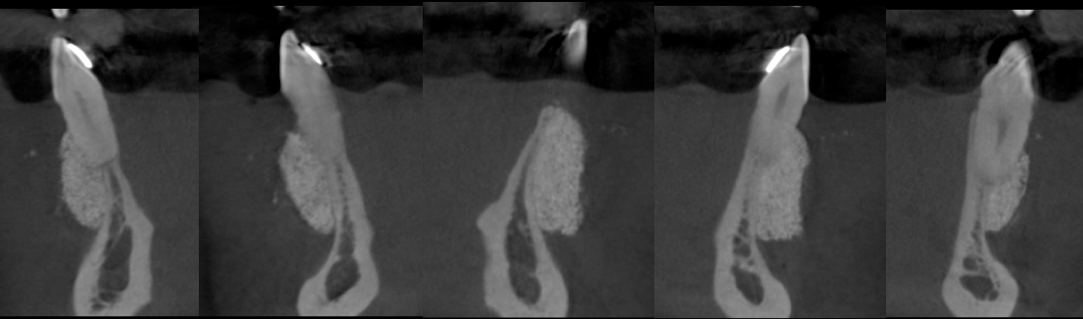

Implants were placed 9 months following the S.M.A.R.T. bone graft. Bone in the vertically grafted areas was hard to drill through the osteotomy process. All implants exhibited excellent primary stability.

Screen Shot 2019-02-20 at 1.13.43 PM.png

With the patient’s consent, a core specimen was harvested during the osteotomy preparation for implant #9(21) and sent for histologic analysis.